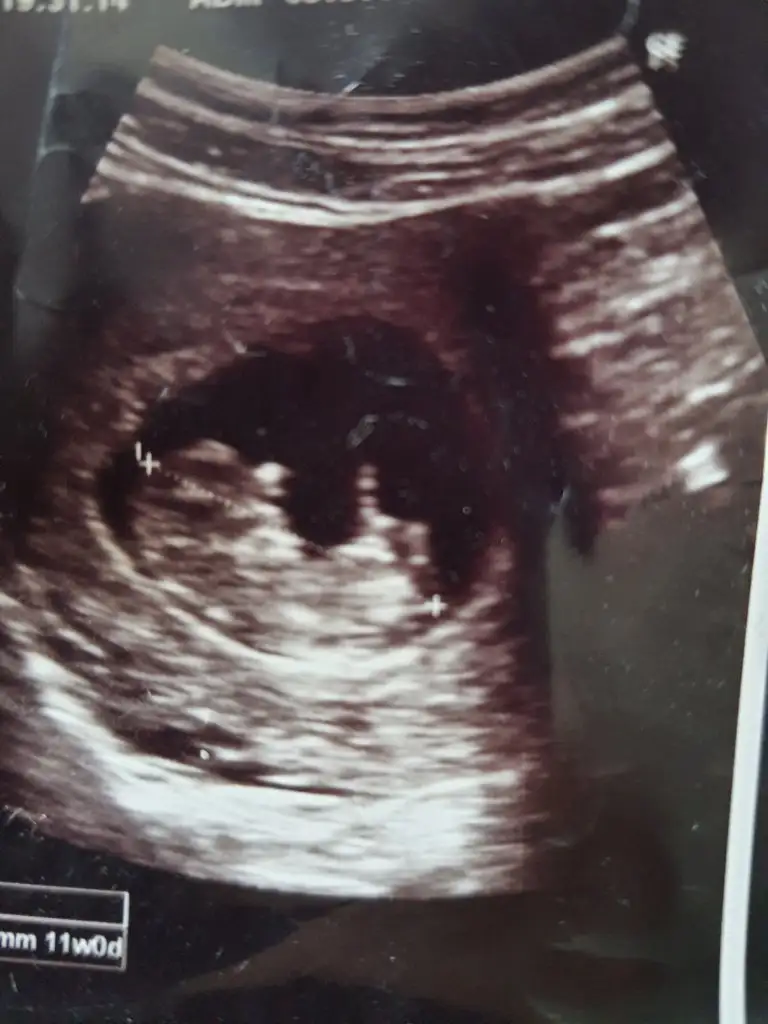

Teşekkür ederim canım suan 13 haftalık oldum sırtı dönük oldugu icin doktor tam göremedi ama %70 kız olabilir dedi 15 hafta olunca tekrar gideceğim ozaman inşallah sırtı dönük olmazSanırım kız gibi geldi bana

Oyyy maşaAllahTeşekkür ederim canım suan 13 haftalık oldum sırtı dönük oldugu icin doktor tam göremedi ama %70 kız olabilir dedi 15 hafta olunca tekrar gideceğim ozaman inşallah sırtı dönük olmaz

Bebeğin konumuna göre kız sanırımBi oglum var onceligimiz saglikli olmasi tabiki ama insan merak ediyor canm banada bakarmisin 8+3 karından